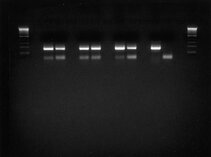

A “core” research team of 2 lab managers is installed at our laboratory to ensure optimal services in developing technical skills of its team members. A variety of standard basic science operations such cell cultures, fluorescence microscopy, Western blot and PCR - just to name some - can be learned at our laboratory.

These images tell a story and we will explain it to you…..